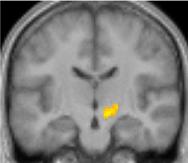

Second, they used functional magnetic resonance imaging (MRI) to investigate what brain region activates when participants observed the android's and the human's movements in the movies, wherein they were only slightly different in naturalness. The subthalamic nucleus is found to be responsible for detecting the android's slight awkwardness.

"Visual observation of the android, compared with that of the human model, caused greater activation in the subthalamic nucleus (STN), which plays an important role in motor control," says Takashi Ikeda, lead author of the study, which was published recently in Scientific Reports .

Notably, the STN is involved in the process of impairing dopaminergic neurons in the deep brain structure in Parkinson's disease patients. Deep brain stimulation to the STN dramatically improves rigidity or impairment of voluntary movement in these patients.